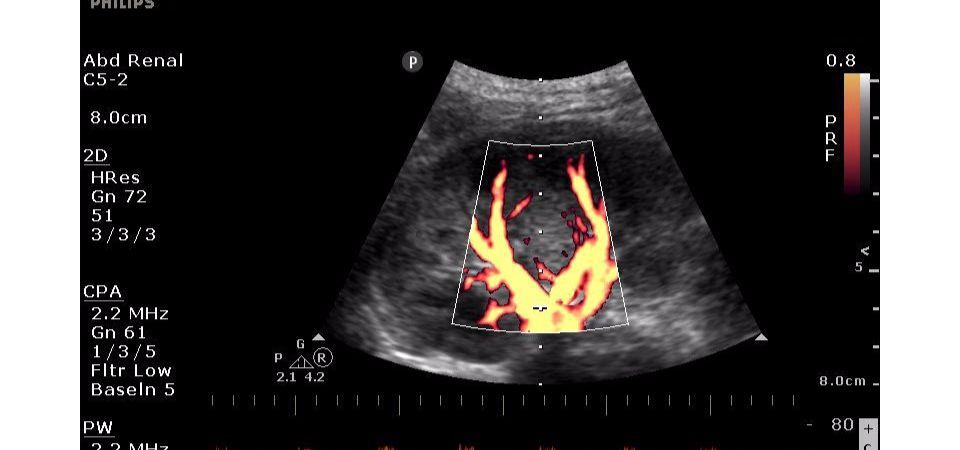

Philips ClearVue 350

Ультразвуковая система ClearVue 350 с технологией Active Array полностью отвечает высоким требованиям Philips к качеству визуализации и помогает повысить достоверность диагностики.

Технология Active Array: Уникальное решение от Philips, при котором основные технологии визуализации интегрированы непосредственно в датчик, обеспечивая превосходное качество изображения при высокой надежности системы.

Технология XRES: Фирменная технология обработки изображений Philips в сочетании с предустановленными настройками датчиков значительно повышает качество визуализации и достоверность диагностики.

• Полный набор допплеровских режимов: CW, PW, CFI, CPA, HPRF PW и триплексный режим

• Конвексный УЗИ датчик Philips C5-2